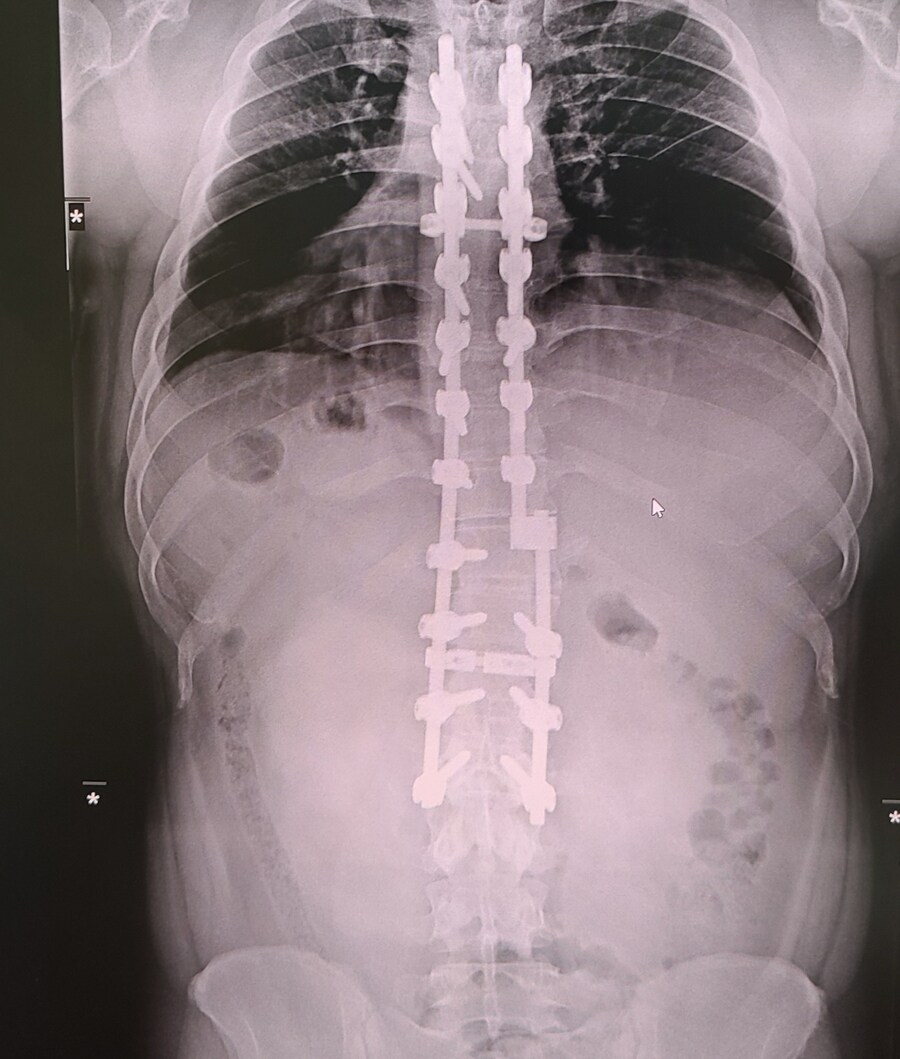

저는 척추후만증 즉 척추가 앞으로 휘는 병입니다.

후만증도 보통 후만증이 아니고 제대로된 병명도없는 극극극극극후만증이었습니다.

얼마나 답도 없었냐 하면 후만증의 진행이 너무 빨라 내부 장기들이 적응하지못하고 다 터져버릴정도의 극한의 후만증이었습니다.

그래서 장기가 터지냐 척추가 터지냐의 환경에서 겨우 수술받고 살아난 케이스입니다.